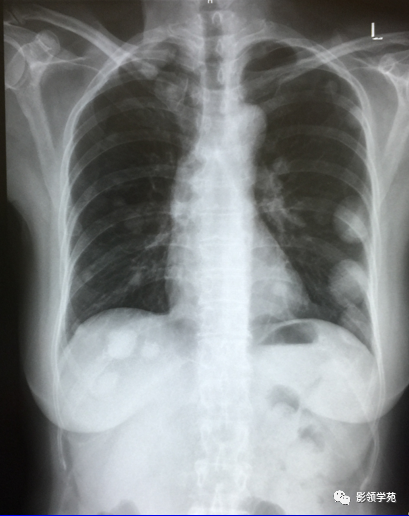

1. 血行性转移 :

多发或单发结节,大小不一,边缘较清楚。少数结节伴出血时出现晕轮征,即有略高密度影像环绕结节,使病变边缘模糊。病变有钙化常见于骨肉瘤或软骨肉瘤转移。转移瘤亦可表现为空洞。两肺多发的小结节影具有随机分布的特点,HRCT显示结节位于小叶中心、小叶间隔、支气管血管束及胸膜,结节大小不均匀。

2.淋巴道转移:

HRCT表现为沿淋巴管分布的结节。支气管血管束结节状增粗,并有结节,小叶间隔呈串珠状改变或增粗,小叶中心有结节灶,并有胸膜下结节。病变在两肺弥漫分布或局限于某一部位,以中下肺多见。常合并胸腔积液。约半数病人有纵隔及肺门淋巴结肿大。